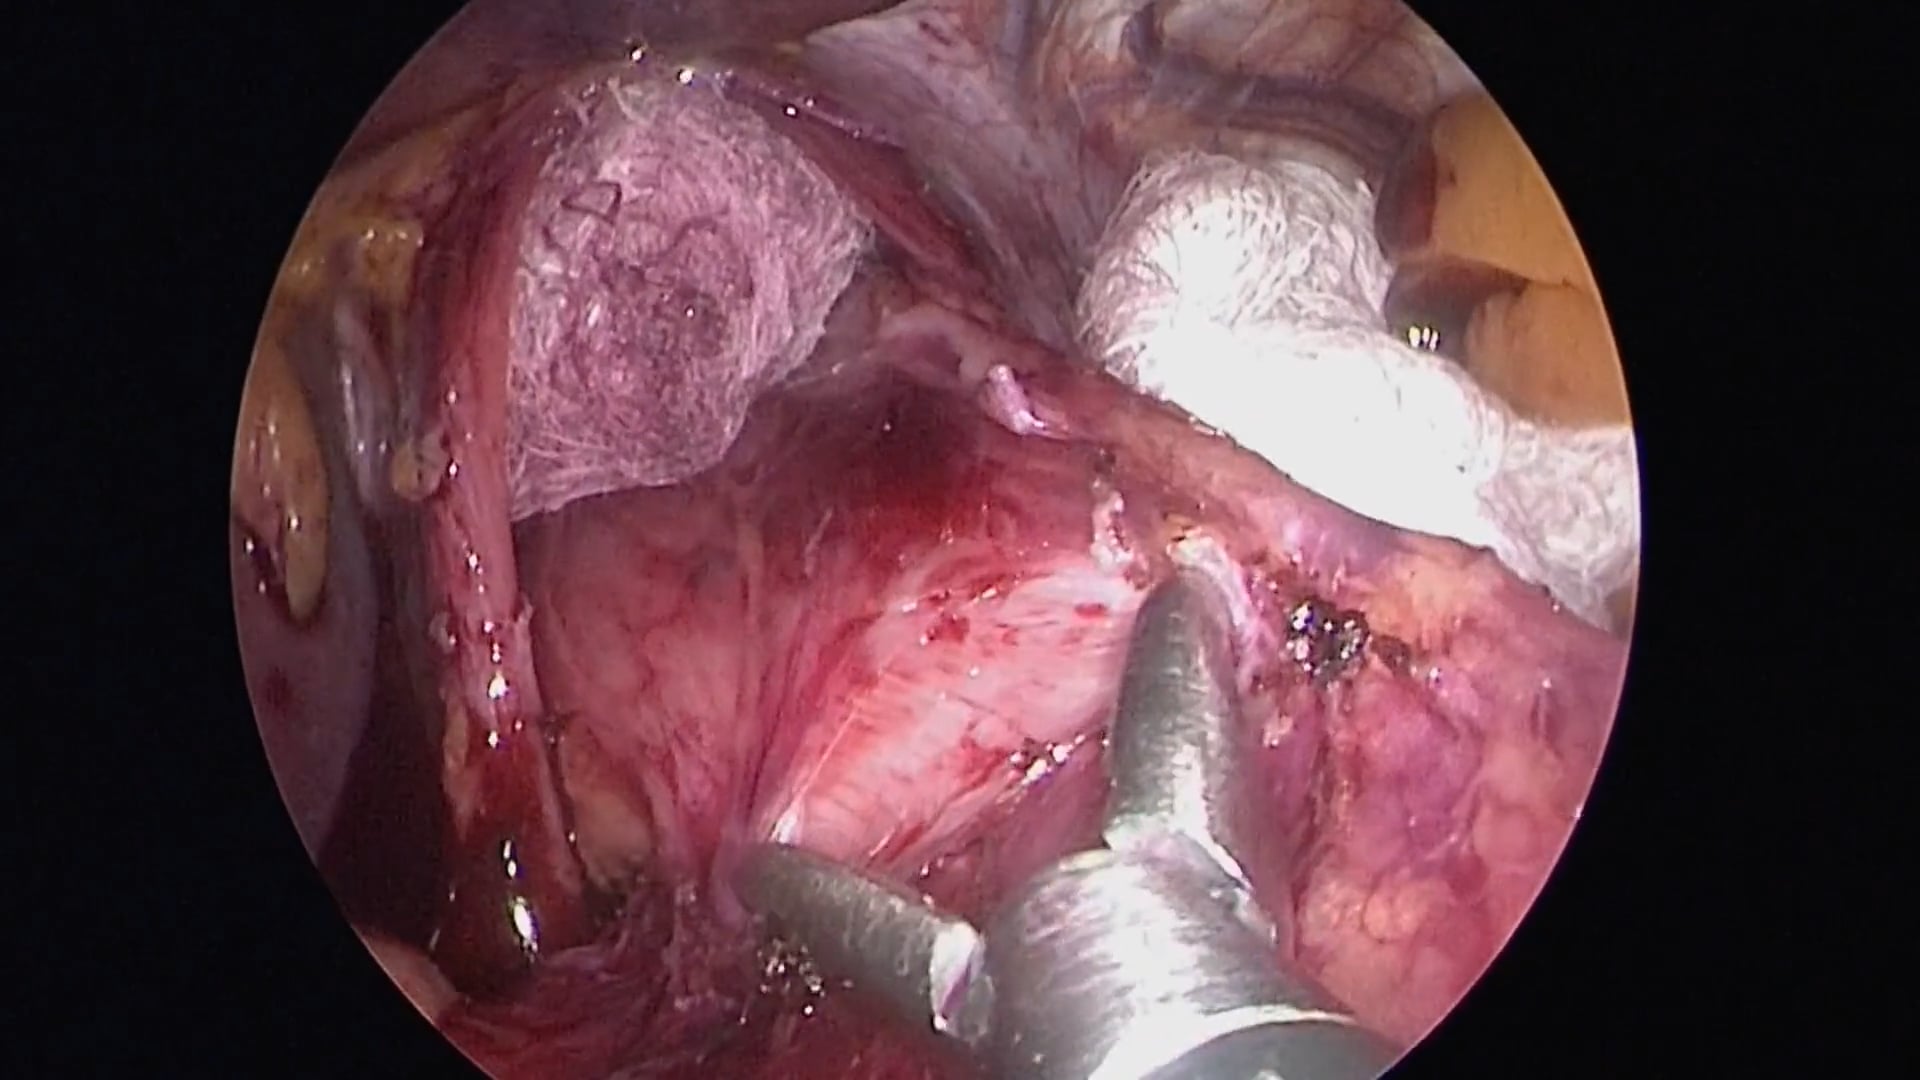

Exérèse totale du mésorectum (TME) robotisée avec section transanale et anastomose par agrafage circulaire : procédure live intégrale

Q Denost, B Noiret, A Forgione, D Kitaguchi